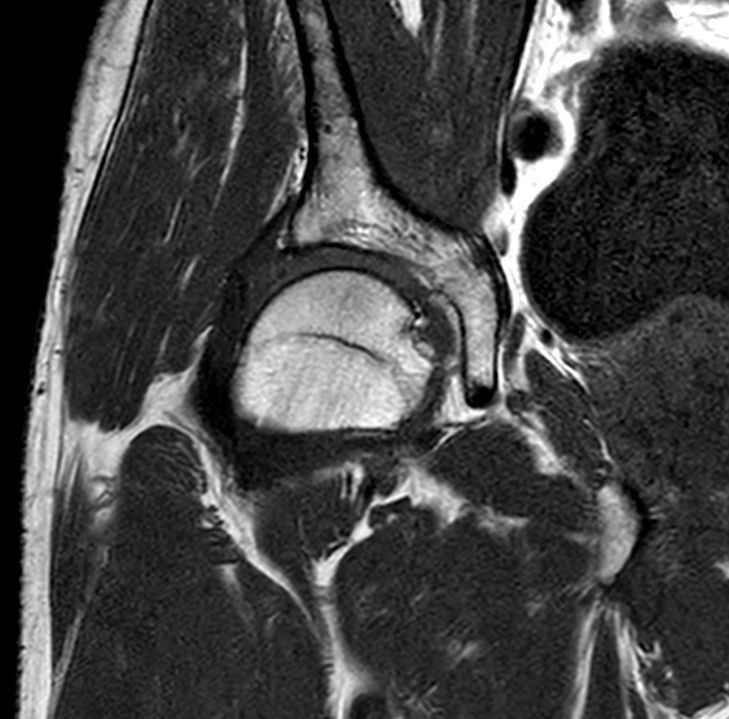

Coronal PDw TSE FatSat

Coronal PDw TSE FatSatSmartSpeed

Coronal PDw TSE FatSatSmartSpeed Resolution